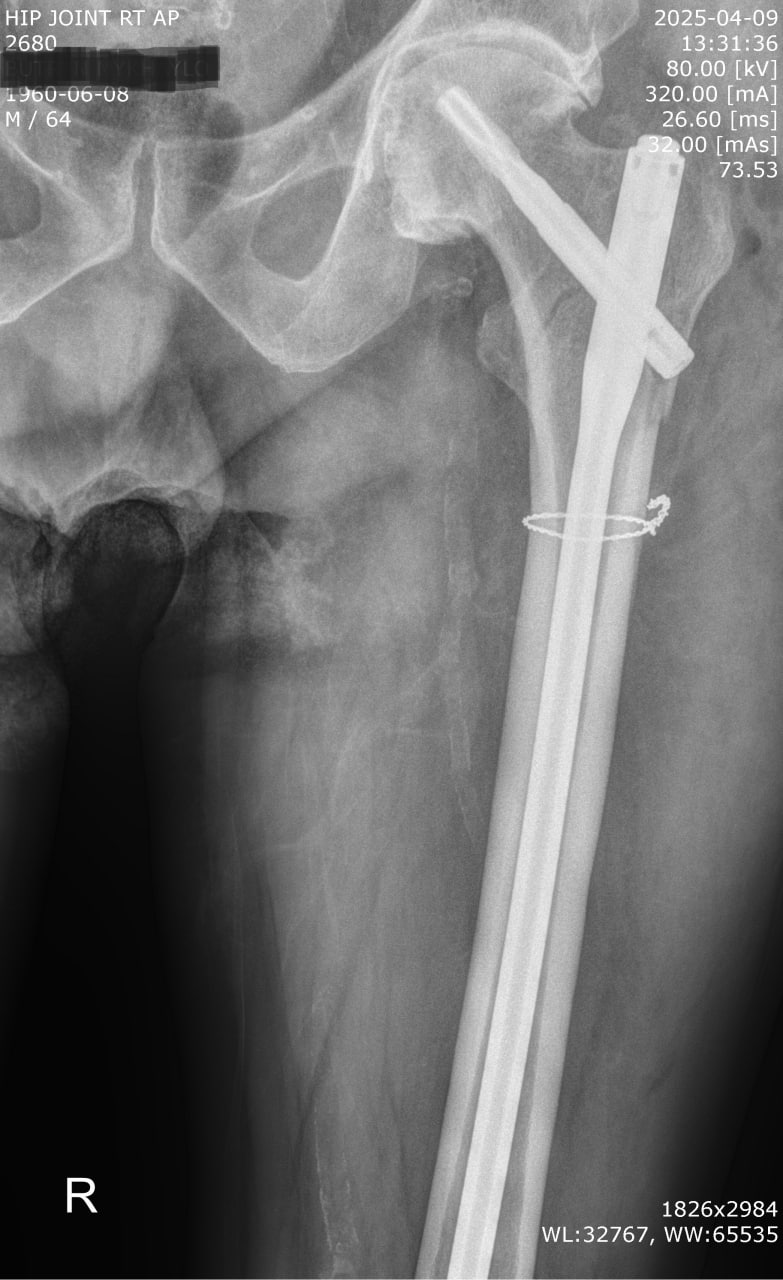

Пацієнт Б., 64 роки. Побутова травма — падіння з висоти власного зросту. Звернувся до травмпункту приймального відділення КНП ТМР «Теребовлянська міська лікарня». Після обстеження встановлено діагноз: закритий підвертельний перелом правої стегнової кістки зі зміщенням уламків.

Обсяг операції включав:

– анатомічну репозицію уламків,

– серкляжну фіксацію,

– інтрамедулярну фіксацію стрижнем PFN-A Long (Proximal Femoral Nail Antirotation) — «золотий стандарт» лікування підвертельних переломів.